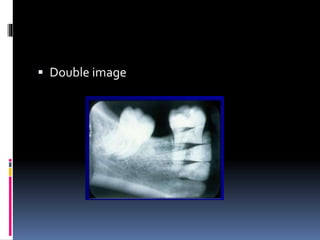

 Double image